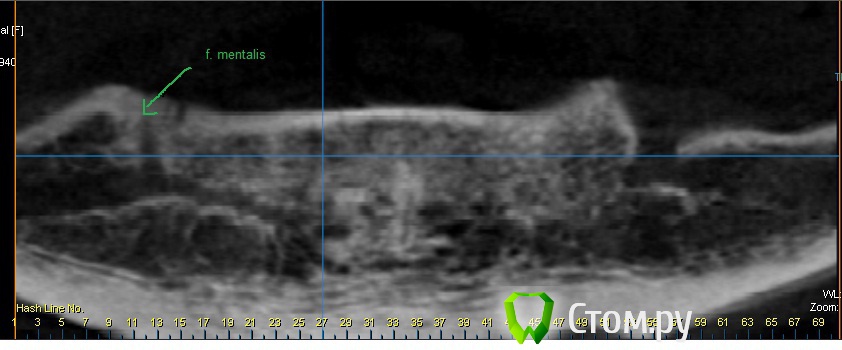

bilal Опубликовано 18 октября, 2014 Поделиться Опубликовано 18 октября, 2014 Как тут быть. Собрался импланты ставить перед ментальными отверстиями для съемного протезирования. А тут оказывается, что нерв после выхода из ментального отверстия продолжается в челюсти почти до серединной линии. Ссылка на комментарий

kriokov Опубликовано 19 октября, 2014 Поделиться Опубликовано 19 октября, 2014 это продолжение учавствует ли в иннервацию мягких тканей? Или смело можно сверлить можно. Вот картинки по иннервации из сети.На картинке где отсутствует кортикальная во фронте виден дополнительная веточка идущая внутрикостно и не учавствующая в иннервации мягких тканей. Мягкие ткани иннервиует ментальный, который выходит из ментальногоhttp://www.imageup.ru/img231/1913915/2014-09-17-20-39-55-skrinshot-ehkrana.jpghttp://www.imageup.ru/img231/1913918/2014-06-07-17-47-59-skrinshot-ehkrana.jpg 2 Ссылка на комментарий